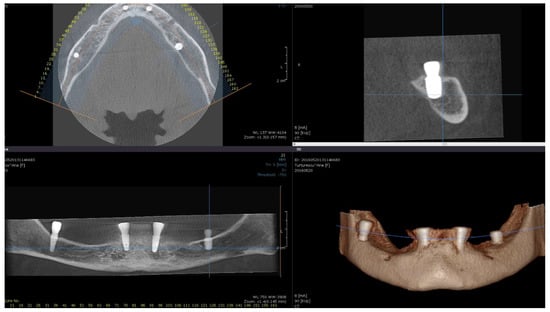

Direct visual access to the residual bone was obtained by elevating a full muco-periosteal flap. A lance drill was used to mark the implant site at approximately 2 mm towards the midcrest with respect to the buccal or lingual cortex. To avoid thermal osteonecrosis, copious cooling irrigation, new drills, and a maximum speed of 800 RPM were used for implant site preparation. After the osteotomy site was marked, a pilot 2 mm drill was selected to perform the preparation for the length of the selected implant. In-and-out manoeuvres were performed in order to facilitate cooling of the drills. If the implant is planned to be placed buccally, the drill must be oriented with the apex faced towards buccal wall, trying to keep the axis of the drill parallel to the buccal cortex. In most of the cases, if the pilot drill direction was properly assessed, minimal or even no bleeding will be observed and the patient will indicate no pain. If the osteotomy preparation was performed buccally, a bone dehiscence might be present. In this scenario, the following drills must be slightly pressed towards the inner wall (wall facing towards the middle of the alveolar crest) of the osteotomy site. This manoeuvre is performed by a digital propelling force on the head of the handpiece, according to the preparation protocol for D1 bone recommended by the implant company. If a 4.0 mm diameter tapered implant (AnyRidge, Megagen Implant Co., Daegu, Republic of Korea) is planned to be used, the following drills were selected for convenient site preparation: 2.7 mm, 3.3 mm, 3.8 mm for the whole length of the osteotomy and a 4.3 mm drill was used only for countersink. Implant insertion was done with the surgical motor (at 35 RPM). A similar drilling protocol is applied for 3.5 mm diameter implants (last drill 3.3 mm and 3.8 mm countersink) and a 4.3 mm drill for the whole length, for 4.5 mm diameter implants. Depending on the thickness of the surrounding soft tissues and the relation with the buccal mucosa, either a 7 mm long healing abutment (I-Gen Kit, Megagen, Daegu, Republic of Korea) or a customized healing abutment was connected to the implant, with digital clockwise rotations. Double layer suture (horizontal mattress and simple suture) was done with 5/0 resorbable suture (Vicryl, Ethicon, New Brunswick, NJ, USA). Patients were prescribed antibiotics (Augmentin®—amoxicillin plus clavulanic acid 1 g/every 12 h) and one tablet of anti-inflammatory drug (Ibuprofen 600 mg at every 8 h) for the following 5 days. Patients were instructed to avoid brushing the neighbouring teeth in the treated area and chlorhexidine solution (0.12%) was prescribed for daily usage (twice a day for 1 min). Sutures were removed after 14 days [16]. All patients were recalled for clinical checkup 1 day, 1 week, 2 weeks, and 2, 6, 12, 24, and 36 months after surgery. All complications, both during the surgery and postoperative, were reviewed. A postoperative CBCT was done to assess implant positioning. Buccally tilted and lingually tilted implant positioning are presented in Figure 1 and Figure 2, respectively.

Figure 2.

Postoperative CBCT of patient no. 5: (Upper left)—axial view of the mandible; (upper right)—sagittal left view of the lingually tilted implant (36); (lower left)—coronal view of the mandible; (lower right)—3D view of the mandible.